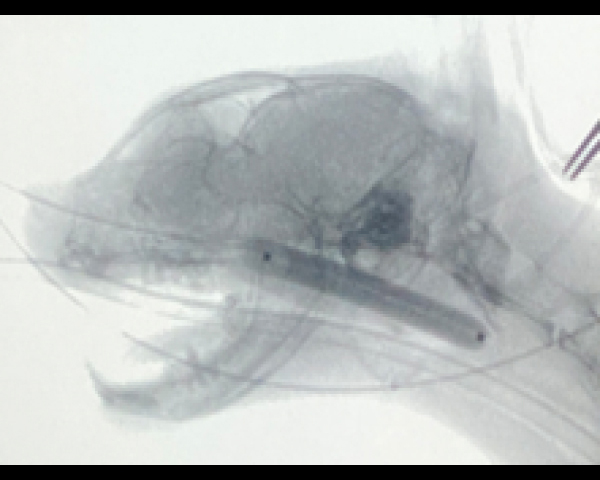

Cアームを用いたバルーン拡張術

拡張後の鼻咽頭部